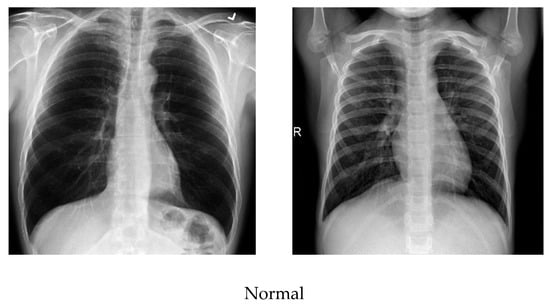

As the number of images available in the open repository was limited, the images from all three databases were combined to create a database for this work. The training and testing stages used both classes: COVID-19-positive and COVID-19-negative. The COVID-19-positive class contained 1979 images, and the COVID-19-negative class contained 3111 images. All data sets were divided into 0.8 portions and 0.2 portions for the training and testing, respectively. A computer having 64-bit windows, 8 GB RAM, Intel Core i5 CPU with a processing speed of 2.60 GHz was used for performing all training and testing. MATLAB 2019b was used to execute all necessary experiments. The experimentation times are computed with a GPU hardware configuration of GEFORCE RTX 2070 super. Figure 3 illustrates a comparison of the COVID-19 and normal chest X-ray images. In general, similar to pneumonia, the density of the lungs is increased in the case of the COVID-19, which causes whiteness in the lungs on radiography. An experienced radiologist can confirm the disease by the appearance of a ground-glass pattern (ground-glass opacity) due to the increased whiteness [46].

Figure 3.

Comparison of the COVID-19 and normal X-ray images.